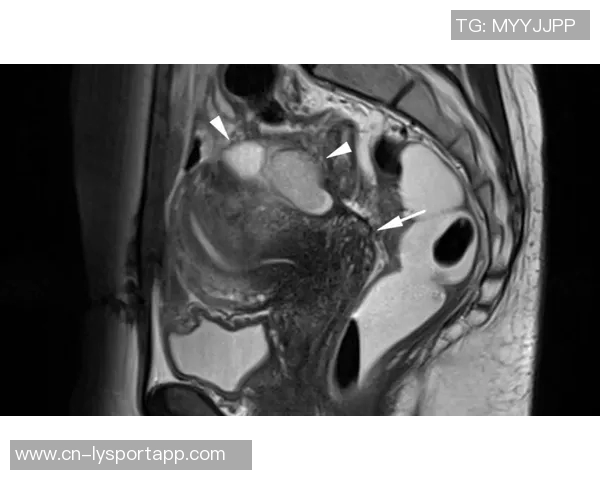

幸运的是,通过X光结果显示并未发现明显异常,这意味着目前没有骨折或严重损害的迹象。然而,这并不代表他完全没有危险,因为软组织损伤如韧带扭伤等问题仍然需要进一步确认。因此,医生建议进行MRI检查以获得更详细的信息。

MRI(磁共振成像)是一种无创性的高分辨率影像学技术,可以清楚地显示软组织结构,因此对于评估肌肉、韧带和其他组织的损伤尤为重要。这也是为什么医生会选择第二次检查,以确保全面了解约维奇的实际情况。